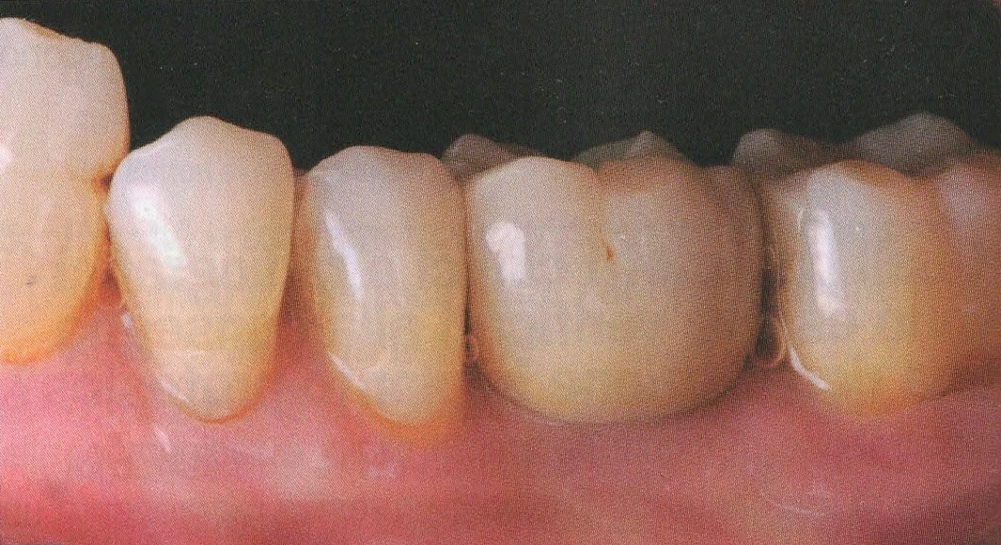

In questo studio vengono eseguite ceramiche di ultima generazione quali la zirconia ceramizzata, le ceramiche estetiche in disilicato senza trascurare le tradizionali metalceramiche. Il disilicato è un materiale altamente estestico che conferisce alla corona protesica un aspetto naturale e con questo materiale si possono creare manufatti con uno spessore molto ridotto.